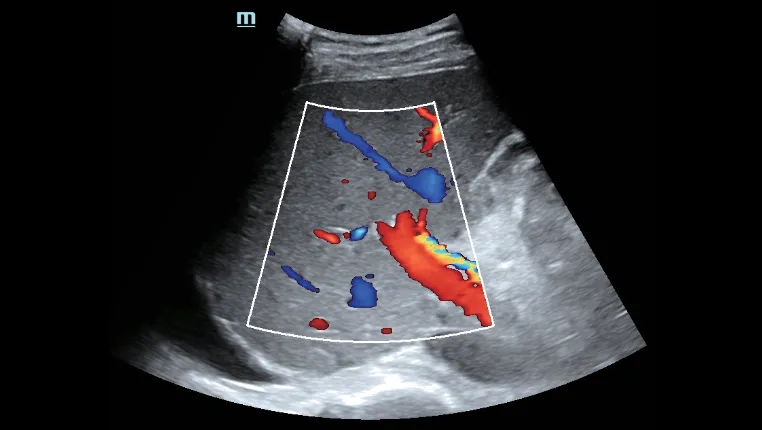

- Превосходное ультразвуковое изображение и функциональность позволяют всесторонне оценить морфологию и гемодинамику печени.

Оценка портальной гемодинамики